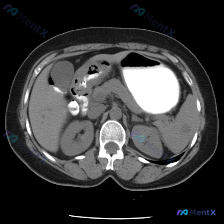

图像层面:上腹部横断面,包含胃体、肝、胆囊、脾及双肾上极水平;图像清晰度良好,无明显伪影,软组织结构辨识度可。胃腔内有高密度造影剂或内容物,肝及腹部血管强化不明显,推测为平扫或增强后较晚期层面。

- 肝脏:形态大致正常,实质密度未见明显异常灶;胆囊清晰,壁不厚,囊内未见结石样高密度影

- 脾脏:形态正常,实质密度均匀,未见占位性病变(划重点)

- 肾脏:双侧形态、大小及密度大致正常,皮髓质界限清,无明显肾积水或结石

- 胃:腔内可见大片高密度影,推测为口服对比剂或特定内容物,胃壁局部显示尚可,未见明显局限性增厚或肿块

- 腹膜后:腹主动脉及下腔静脉走行清晰,无明显增宽或夹层;椎体骨质密度未见破坏;腹腔内无游离气体或积液

主要异常发现:在十二指肠降部及胰头部前方区域,可见团块状高密度影,边缘有空气密度影(低密度区)及造影剂混合,呈现复杂的影像特征。